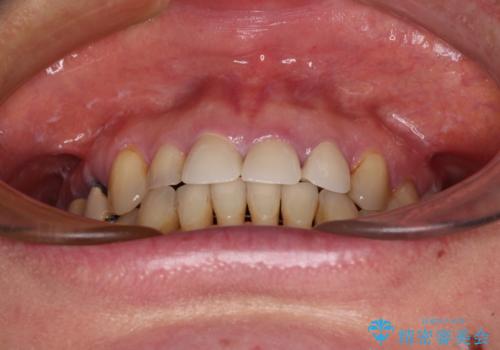

反対咬合や欠損を治療したい インビザライン矯正とオールセラミックブリッジ

- 虫歯治療がうまく進まないとのことで来院された患者様です。

虫歯治療や欠損補綴治療も必要でしたが、前歯が反対咬合であったので、セラミッククラウンやブリッジによる治療と並行して矯正治療を提案しました。

仕事柄海外出張が多いとのことで、虫歯治療後にインビザラインにて矯正治療を行うこととしました。